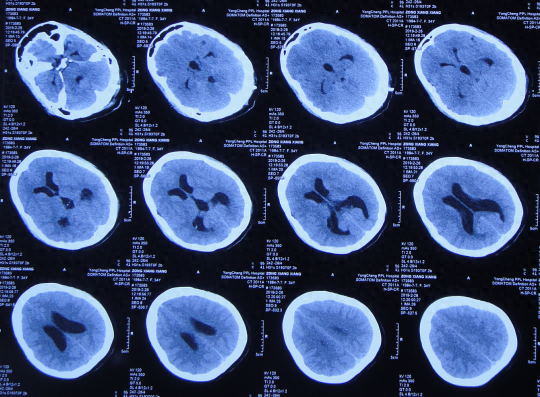

小脑扁桃体下疝减压术后28天即2019年3月14日,仍头痛剧烈,间断发热,转至上级的河南省郑州市某三甲医院。于2019年3月15日,查头颅CT(图-10)后进行了腰大池引流治疗,引流后头痛仍无缓解,引流出脑脊液呈淡黄色,浑浊,考虑颅内感染。

图-10:2019年3月15日头颅CT

入院当天头颅CT示小脑扁桃体下疝减压术后,枕下可见低密度影。脑室系统稍扩张(图-12);颈椎核磁脊髓可见空洞形成(片子丢失)。

图-12:2019年3月19日入院时头颅CT

图-13:入院当天术后头颅CT

入院治疗3天即2019年3月22日,头痛减轻(图-14),查头颅CT示较入院时缩小(图-15)。

图-15:2019年3月22日头颅CT

入院治疗48天即2019年5月15日,进行了右侧脑室-腹腔分流术(图-17)。

图-17:2019年5月15日头颅CT